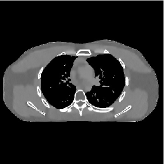

![]() |

| (a) 2D fan-beam CT experiments |

This section compares the reconstruction quality and runtime among the proposed MBIR method, PWLS-ST-, and other three MBIR methods, PWLS-EP, PWLS-DL, and PWLS-ST-. Table I shows that, for both 2D and 3D sparse-view CT reconstructions of the XCAT phantom, the proposed PWLS-ST- model outperforms PWLS-EP and PWLS-ST- in terms of RMSE. In addition, PWLS-ST- using a square transform (of size ) achieves lower RMSE than PWLS-DL using an overcomplete dictionary (of size ) for 2D sparse-view reconstructions. Fig. 3(a) and Fig. 4 show the reconstructed images for 2D and 3D phantom experiments, with different reconstruction models and different number of views. (See the corresponding error maps in the supplement.) The proposed PWLS-ST- consistently gives more accurate image reconstructions compared to other MBIR methods. Specifically, PWLS-ST- has smaller errors in the heart region (see zoom-ins in Fig. 3(a)) of 2D reconstructions than PWLS-DL and PWLS-ST-. In addition, compared to PWLS-ST-, PWLS-DL and PWLS-ST- have some ringing artifacts around the edges with high transition, e.g., edges between air and soft tissues. (See a comparison of profiles of PWLS-ST- and PWLS-ST- in the supplement.) In particular, PWLS-ST- and PWLS-DL give more visible ringing artifacts for 2D reconstruction from fewer views, and PWLS-ST- has these ringing artifacts for 3D reconstructions regardless of the number of views (see zoom-ins in Fig. 4). Table II reports runtimes of different MBIR methods in reconstructing the -views XCAT phantom scan. (FBPConvNet is a non-MBIR method and its runtime for processing a image is approximately one second with a TITAN Xp GPU.) While providing better reconstruction quality, the proposed Algorithm 1 of PWLS-ST- has shorter runtime compared to the algorithms of PWLS-DL and PWLS-ST- in Section III-A. Similar to the PWLS-EP algorithm, the reconstruction time of the PWLS-DL, PWLS-ST-, and PWLS-ST- algorithms can be further reduced by using ordered subsets [51].

Fig. 3(b) shows that when tested on the clinical scan data, the proposed PWLS-ST- method improves reconstruction quality in terms of noise and artifacts removal (e.g., see zoom-ins for soft-issue regions), and edge preservation (e.g., see zoom-ins for bone regions), compared to PWLS-EP and PWLS-ST-. Compared to PWLS-DL, PWLS-ST- achieves comparable image quality, but requires less computational complexity.